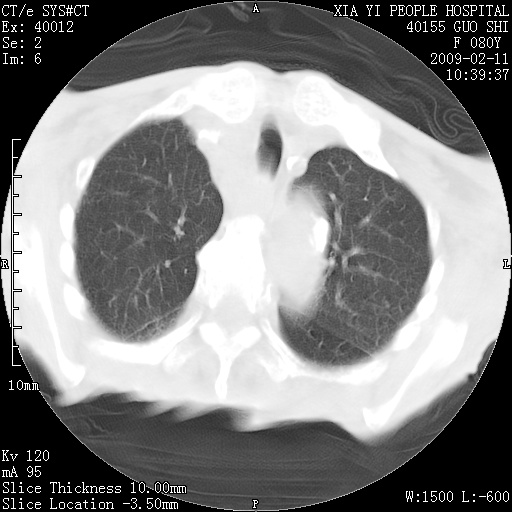

以下是引用随光逐影在2009-2-16 16:34:00的发言:[br]1)考虑右前纵隔皮样囊肿。2)双侧少量胸腔积液。

以下是引用zjzjr在2009-2-16 17:30:00的发言:[br]支持囊性畸胎瘤 双侧少量胸腔积液。